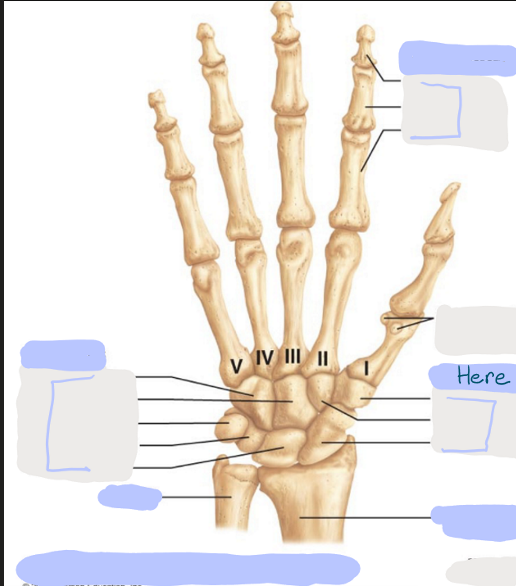

What is this picture of?

Anterior View of the Right Hand

What is here?

Where is the Ulna?

What is here?

Where is the Radius?

What is here?

Where are some of the Carpals?

What is here?

Where are some of the Carpals?

What is here?

Where are the Phalanges?